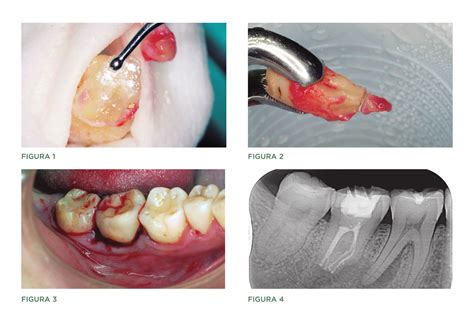

El reimplante intencional consiste en la extracción atraumática premeditada del diente con el fin de realizar un tratamiento endodóntico o para tratar lesiones radiculares inaccesibles, y posteriormente reintegrarlo a su posición original. Con esto se persigue preservar el órgano dentario y evitar extracciones ocurridas por complicaciones específicas o debido a la decisión particular del paciente.

- Extracción atraumática: En casos donde el empleo de elevadores se encuentra contraindicado debido al riesgo de provocar traumas al ligamento periodontal donde se hallan las células requeridas para la óptima reinserción. La descontaminación es realizada en la porción apical del alveolo.

- Tiempo de manipulación extra oral meticulosa: No debe exceder el lapso de 15 minutos. Bajo esta condición se reduce el daño al ligamento periodontal reteniendo la corona del diente con una gasa estéril humedecida en solución o empleando los fórceps en la extracción. Posteriormente, se realiza la valoración de la superficie radicular con magnificación.

- Retrobturación o sellado con material biocerámico: Con un tiempo rápido de fraguado proporcionando un alto sellado. Su bioactividad estimula la mineralización y la recuperación del tejido sano al producir precipitación de cristales de hidroxiapatita en la superficie dentaria.

- Restitución del diente al alveolo: Presionando levemente, sólo en casos de presencia de raíces cortas o carencia de hueso interproximal se encuentra indicada la ferulización.

La extracción y reimplante intencional es el tratamiento indicado en casos donde el tratamiento endodóntico fracasa y por la anomalía dental, la cirugía periapical también fallaría porque solo se eliminaría la lesión momentáneamente más no la que lo causa que es la comunicación entre la cavidad oral y la zona apical.